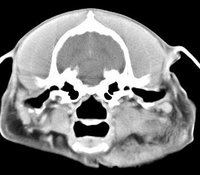

imágenes de TC en el perro | ||||||||||

ejemplo de imágenes de TC en el perro. Nótese la celulitis en la región parotídea izquierda | ||||||||||